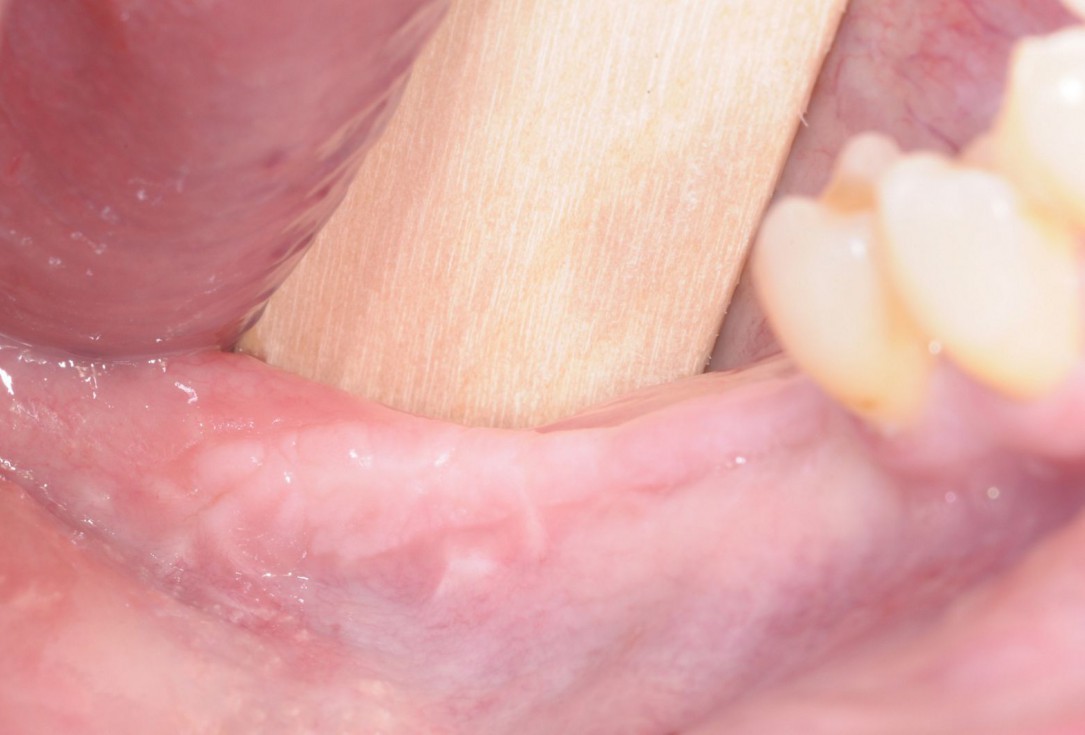

15/28 - Clinical situation 5 months after ridge augmentationThree-dimensional augmentation with maxgraft® cortico - Dr. R. Würdinger